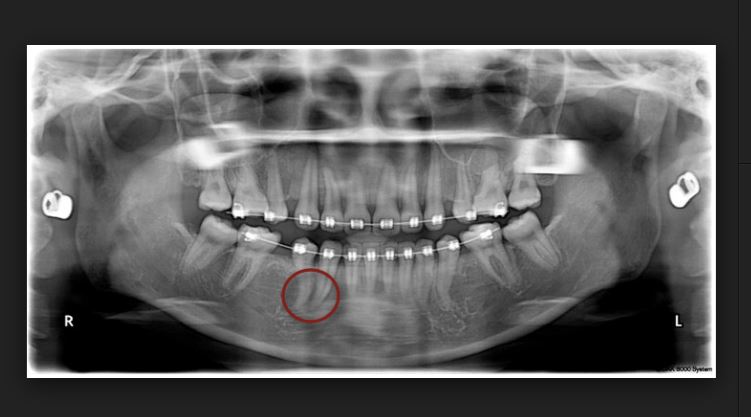

치아교정을 받는 대부분의 환자에서 어느 정도의 치아 뿌리(치근) 흡수 또는 치아 뿌리가 짧아지는 현상이 나타나는데 그 정도가 미미한 정도 1미리에서 1.5미리 정도 라면 큰 문제가 되지 않지만 2미리 이상 치아 뿌리(치근)이 흡수되는 경우에는 정상적인 치아 사용에 문제를 야기시킬 수 있다. 특히 한번 짧아진 치아뿌리(치근)은 다시 길어지는 경우가 극히 드물기 때문에 여러 가지 부작용 중 매우 중요하다고 볼 수 있다.

다른 치아보다 더 흡수가 잘 되는 치아가 있는데 특히 앞니가 이에 속한다. 자연적으로 치아 뿌리는 나쁜 버릇 손가락을 빨거나 손톱을 물어뜯는 나쁜 습관을 장기간 방치하면 앞니 치아 뿌리가 짧아는 현상을 볼 수 있는데 그런 경우 보다 교정시 치아 뿌리 흡수는 더 안 좋은 경우가 많다. 치아가 이동하면서 치아 뿌리 흡수가 일어 날수 일아나면 세심하게 지켜본후 그 정도가 심하면 충치나 나 근관치료등 다른 영향으로 비롯되었는지를 확인한 후 교정치료를 멈추고 신경치료나 충치치료를 한 후 다시 치아교정을 해야 하는 경우도 있으니 교정 후 치아가 많이 흔들리고 뿌리 부분이 너무 아프다고 생각될 때에는 정밀한 검사를 한 후 치아교정을 하는 것이 좋다.

치아교정을 받는 중에는 외상을 특히 조심해야 하는데 치아가 외부로부터 충격을 받으면 빠른 속도로 치아 뿌리가 흡수될 수 있으니 반드시 전문의와 정밀한 진단을 하는 것이 필요하다. 외상을 받은 치아는 평상시는 아무런 느낌이 없지만, 식사를 할 때 치아가 아프거나 시리면 참지 말고 치과에 가서 진단을 받아야 한다.